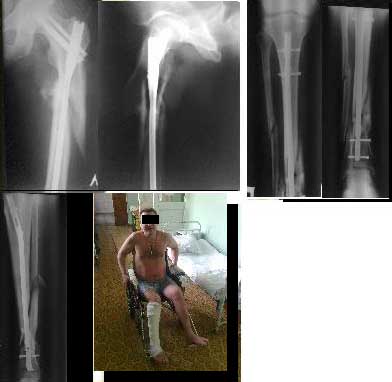

30/09/2011 синтез левого бедра PFN длинный на ортопедическом столе в закрытую.

5.10.2011 синтез правой голени стержнем Деост, в закрытую с применением дистрактора и остеотомией малоберцовой кости. Снимкти в приложении. Пациент активизирован, начал передвигаться на коляске, сегодня встал с костылями.